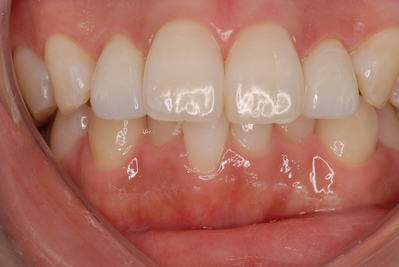

SET後

ラミネートベニアはもちろんセラミック。

e-MAXです。かなり強度があります。

接着はリンクマスターで接着。